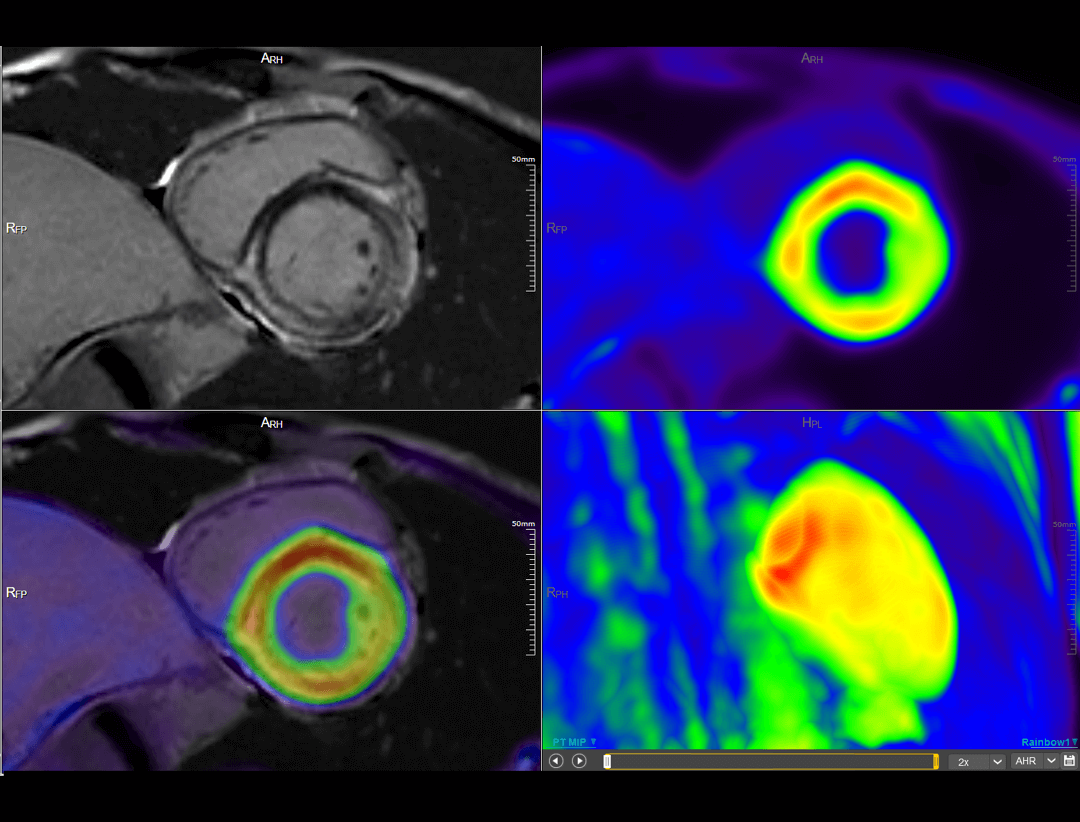

Cardiac Imaging

The uSync research platform enables new levels of PET/MR research with simultaneous encoding of MR sequences, list-mode PET data, and physiological information into the same raw data stream, fulfilling space-time synchronization. This functionality facilitates new research opportunities, including simultaneous tracking of PET and MR tracers, simultaneous cardiac PET and MR, functional neurological PET/MR, and multi-parametric radiomics.